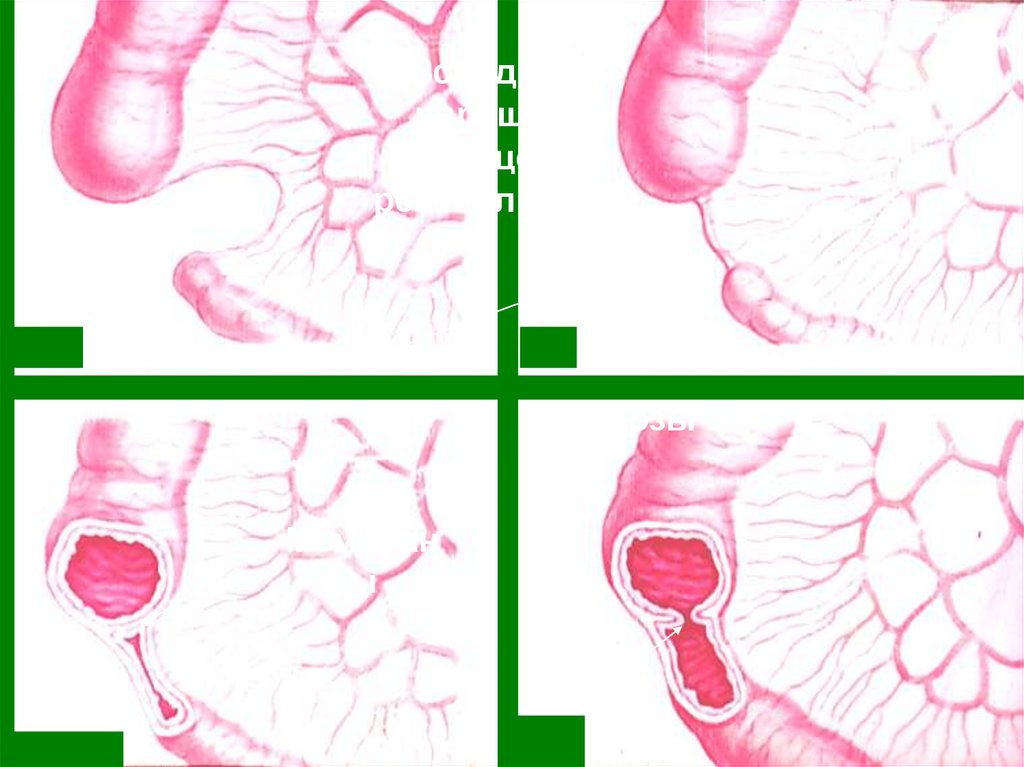

кишечника.

4. Пороки развития кишечной стенки.

5. Муковисцедоз.

6. Нарушение редукции желточного

протока.

53. Тонко-толсто- кишечная инваги- нация.

Тонкотолстокишечная

инвагинация.

54. Толсто-толсто и тонко-тонкокишеч-ная инвагинация

Толстотолсто и

тонкотонкокишечная

инвагинация